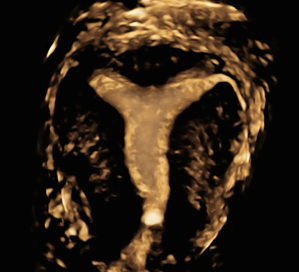

Kromě prenatální ultrazvukové diagnostiky nabízíme i ultrazvukovou hysterosalpingografii pomocí pěny ExEmFoam (HyCoSy). Jedná se o vyšetření pro pacientky, které mají problémy s početím a které dokáže v mnoha aspektech nahradit komplikovanější laparoskopické vyšetření vyžadující hospitalizaci. Jedná se o ambulantní vyšetření, během kterého se provádí 3D ultrazvuk dělohy k odhalení případných vad dělohy a pomocí speciální pěny se vyšetřuje průchodnost vejcovodů. Výkon je šetrný, rychlý a nebolestivý (vyšetření může být mírně nepříjemné).